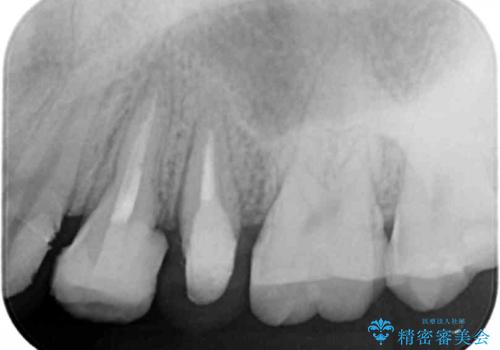

X線撮影を行い、隣接面に多発した虫歯と歯ぐきよりも深くなってしまった虫歯を小矯正をおこなったのちのセラミック治療で問題を解決します。

小矯正を行い深い虫歯を改善した後は、小手術を行うことで歯ぐき・周囲歯槽骨の状態を整えることでより安定した歯周環境を得ることができます。